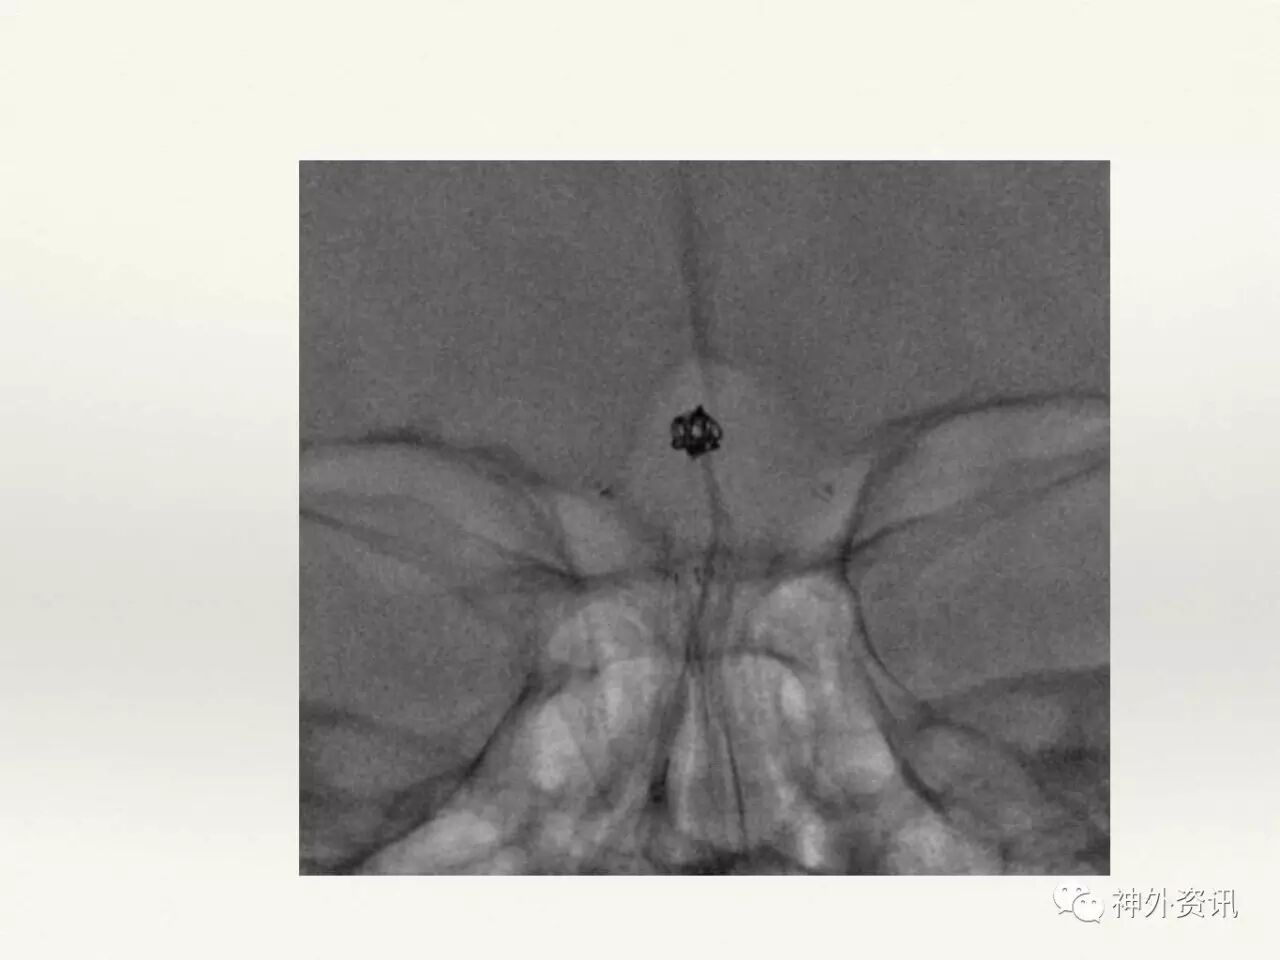

在东北地区率先开展了颈内动脉、大脑中动脉及基底动脉闭塞血管内再通、颅内动脉栓塞急性期取栓、血流导向装置治疗大型宽颈动脉瘤等,对颅内动脉瘤、动静脉畸形、颈动脉及颅内动脉狭窄、颈内动脉海绵窦瘘、硬脑膜动静脉瘘等外科治疗具有较深的造诣。完成脑血管造影8600余例,各类脑血管病介入手术共4500余例,动脉瘤、动静脉畸形、脑肿瘤、脑出血及脑外伤等外科手术1500余例。